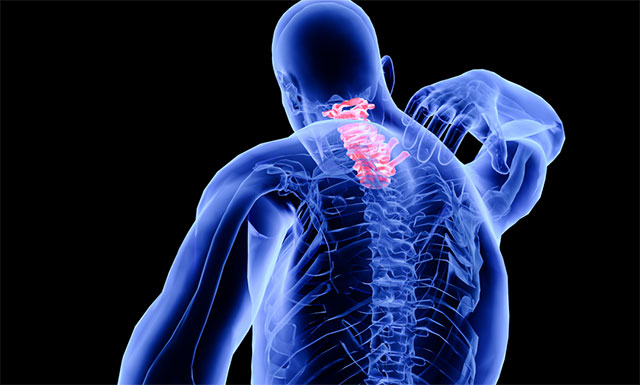

脊髓空洞症是脊髓的一种慢性、进行性的病变。其病变特点是脊髓(主要是灰质)内形成管状空腔以及胶质(非神经细胞)增生。常好发于颈部脊髓。当病变累及延髓时,则称为延髓空洞症。流行病学数据表明,该病每10万人群中约2-8人发病,多见于20-50岁,女性多于男性,是一种比较少见的疾病。

▲ 脊髓空洞症示意图

脊髓空洞症则是由于各种先天或后天因素导致产生进行性脊髓病的脊髓空穴样膨胀,临床表现为节段性、分离性感觉障碍、节段性肌肉萎缩和传导束性运动、感觉及局部营养障碍。脊髓空洞症分为交通性和非交通性两大类:交通性脊髓空洞症意指空腔与脊髓中央管相通,是一种脑脊液通路的液体动力学障碍疾病。反之,非交通性脊髓空洞症只是脊髓内的囊性扩张,不与脑脊液通路相连。